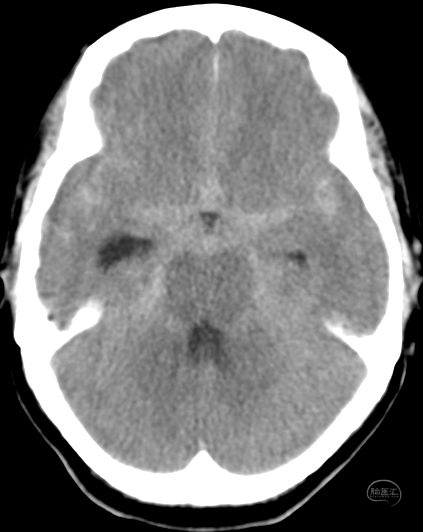

头颅CT提示前纵裂,鞍上池,双侧外侧裂广泛蛛网膜下腔出血

DSA提示右侧后交通分叶状动脉瘤